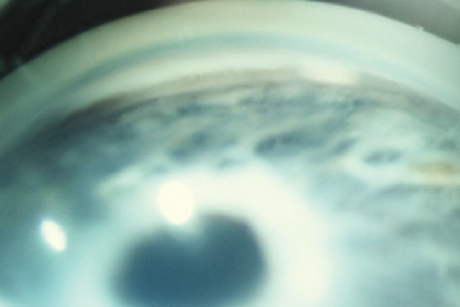

Unlike SLT, this technique can be used in patients with POAG regardless of the degree of pigmentation of the drainage zone structures (Fig. 1, 2) [1, 2].

Fig. 1. Low degree of anterior chamber angle pigmentation (gonioscopy)

Рис. 1. Слабая степень пигментации структур угла передней камеры (гониоскопия)

Fig. 2. High degree of anterior chamber angle pigmentation (gonioscopy)

Рис. 2. Выраженная степень пигментации структур угла передней камеры (гониоскопия)